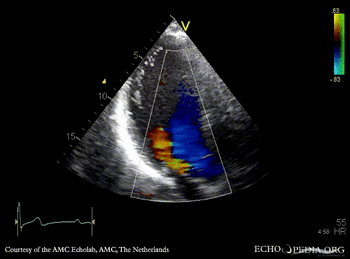

E00233.gif E00234.gif

A4CH: left ventricle dilatation A3CH: Color Doppler, severe aortic regurgitation